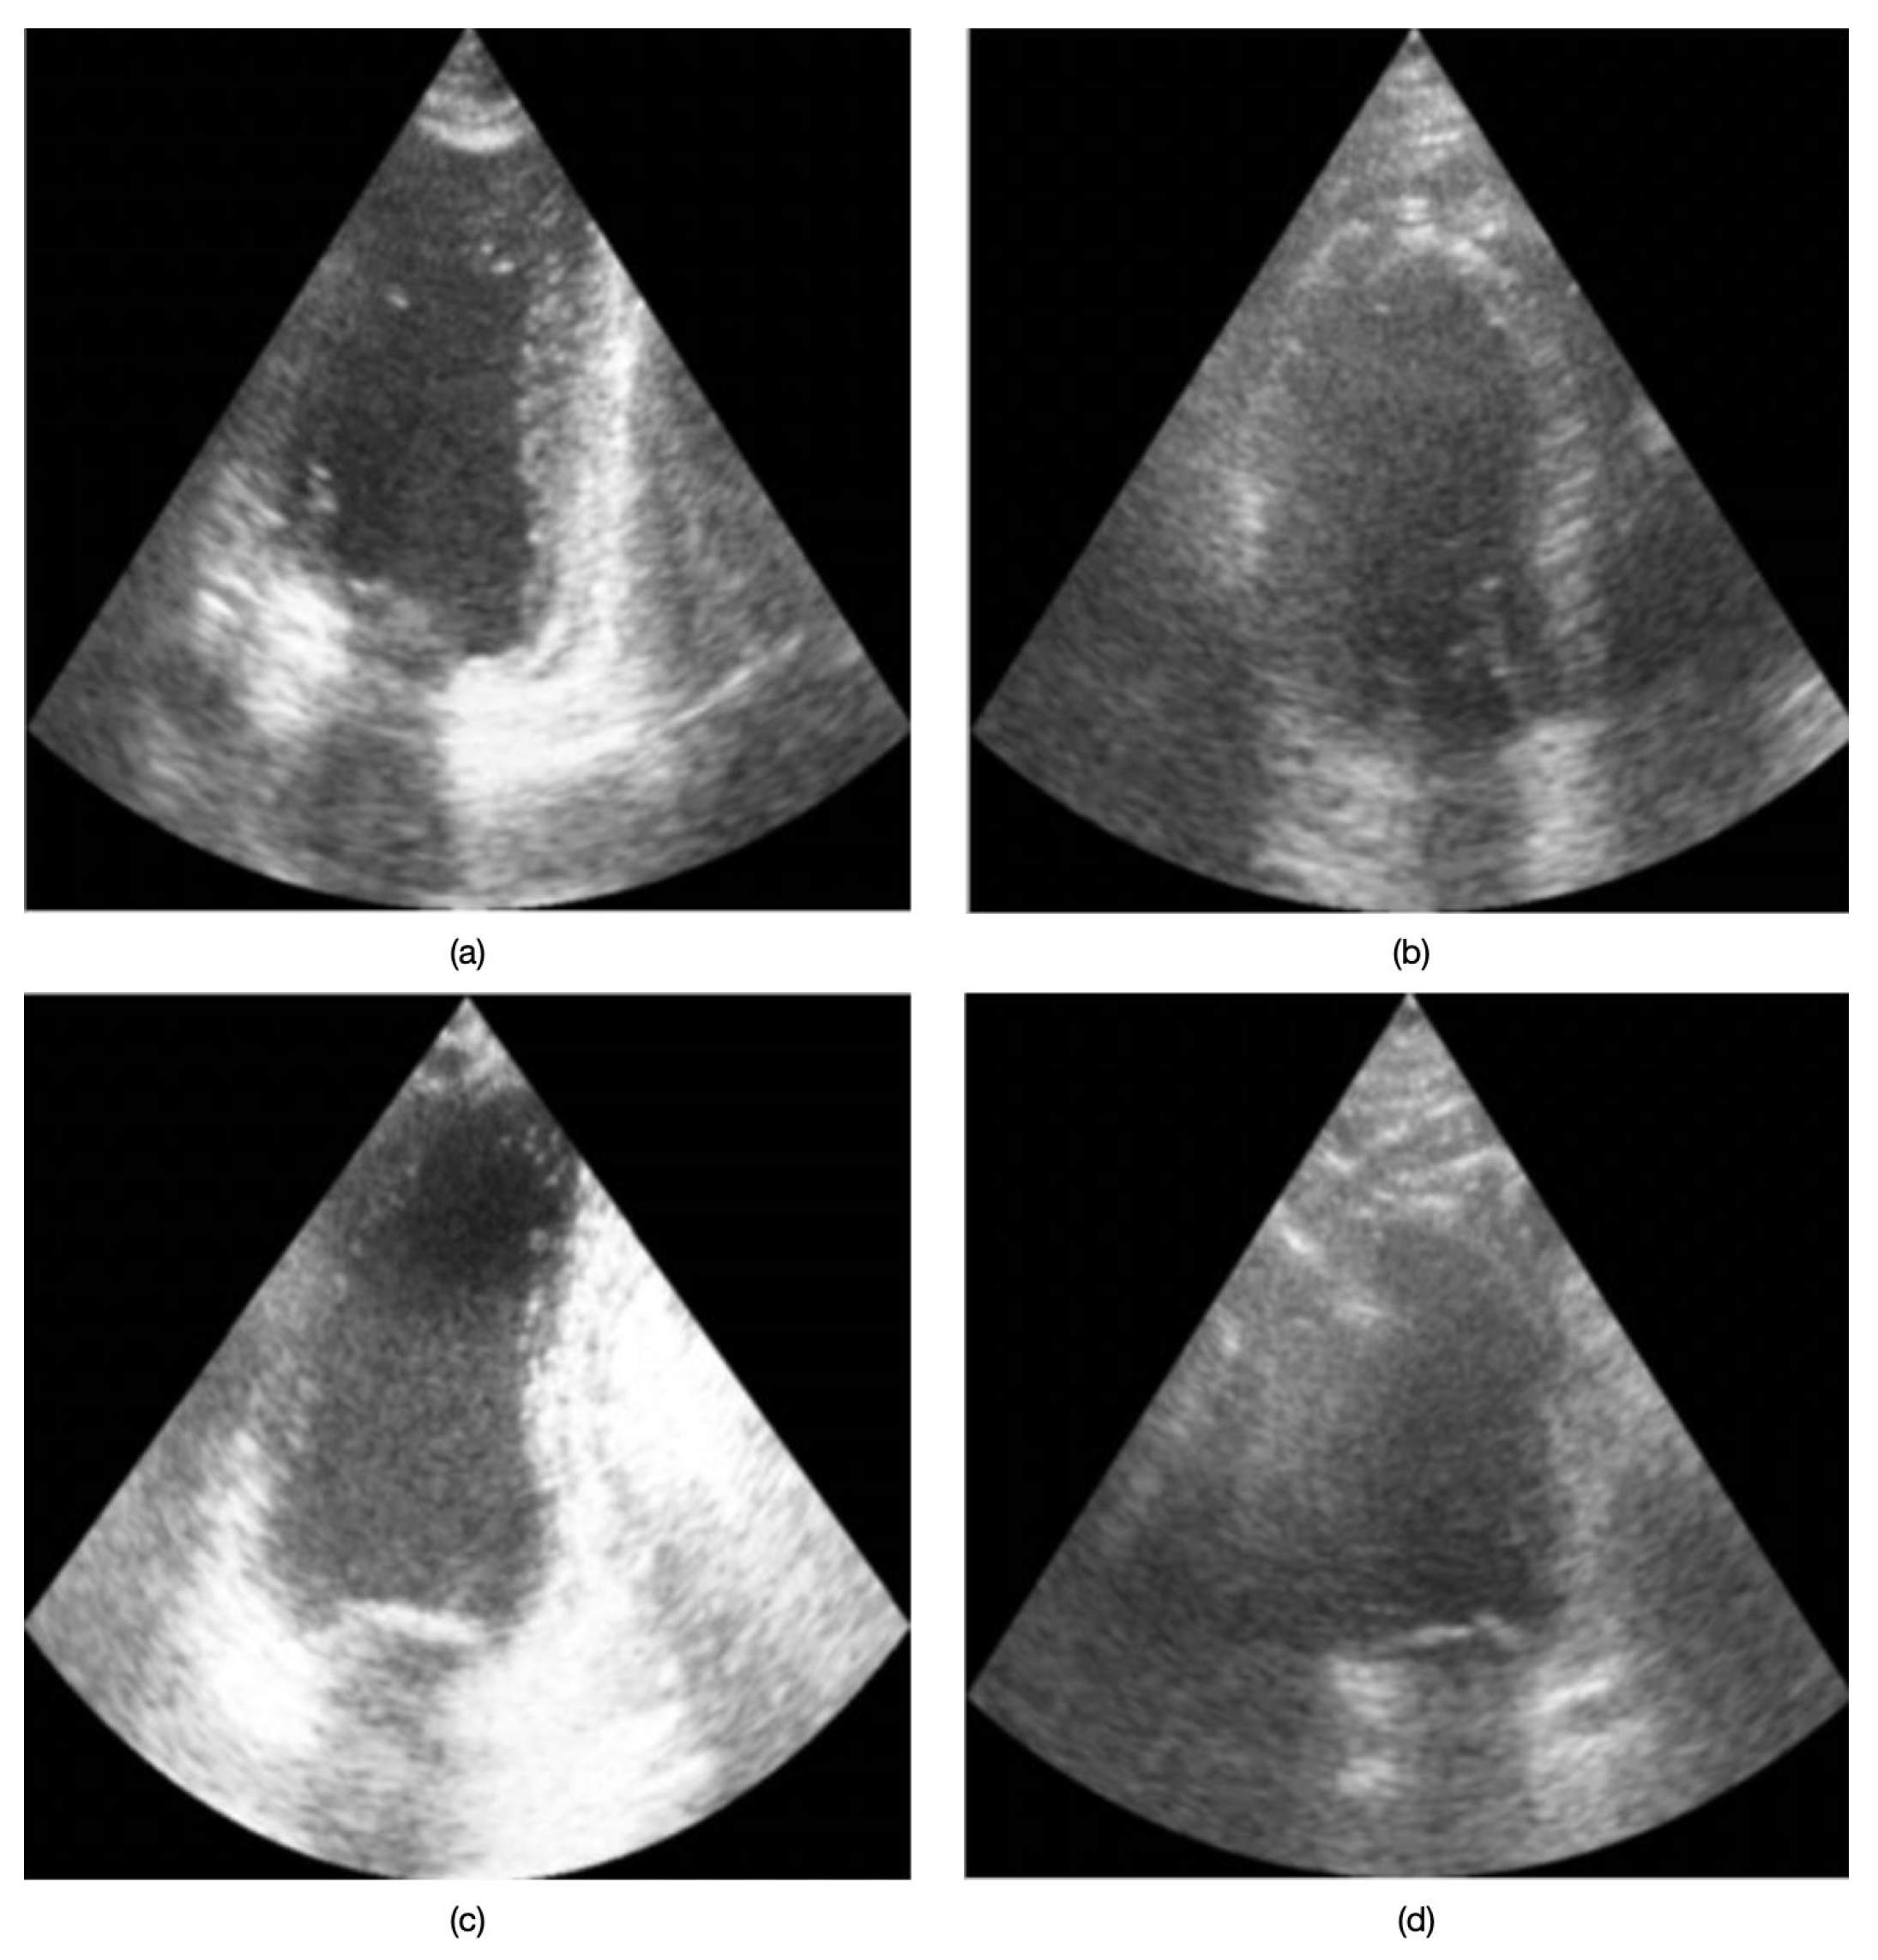

A second CNN was trained on the same dataset to perform binary classification of image quality, distinguishing between “good quality” and “bad/poor quality” for each frame. In this study, we define “good quality” images as those displaying clear anatomical structures, adequate contrast, and minimal artifacts, whereas “bad/poor quality” images exhibit significant noise, low contrast, or insufficient structural visibility. Figure 2 presents example echocardiographic images acquired in both four-chamber (4CH) and two-chamber (2CH) views under varying quality conditions. No data from the inertial sensor were taken into account during the training and inference phases of the two models.

Figure 2. Examples of 4CH and 2CH cardiac views at different quality levels: (a) 4CH good quality, (b) 4CH poor quality, (c) 2CH good quality, and (d) 2CH poor quality.